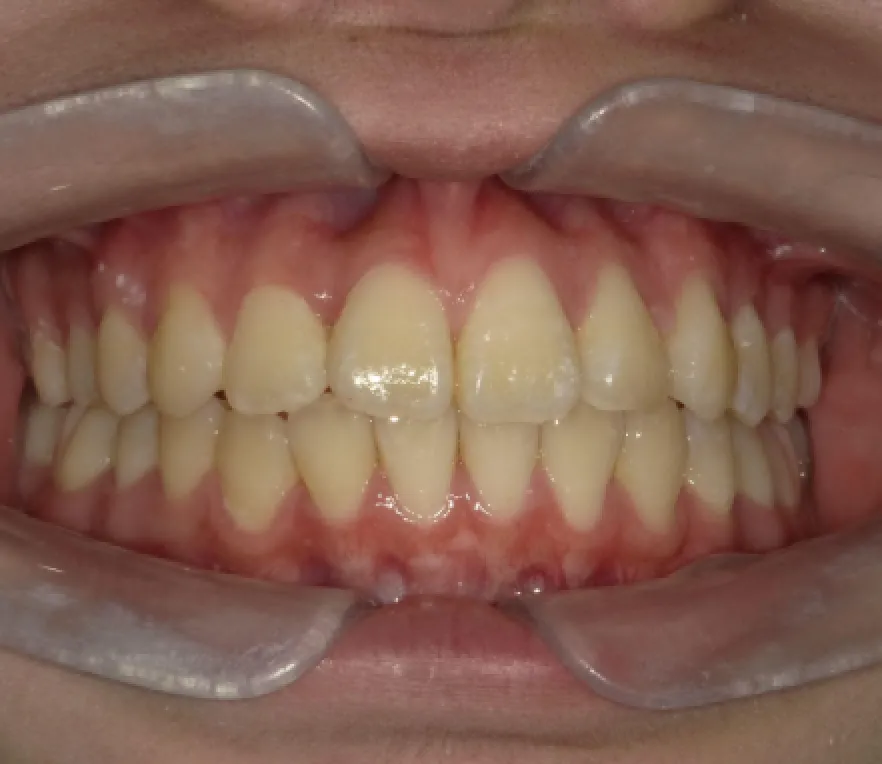

Before

After

性別

年齢

治療費用

治療内容

リスク

副作用

治療期間

女性

10代

902,000円

2年11ヶ月

インビザライン

矯正治療の一般的なリスクといた

しましては、治療中のお痛み・歯

根吸収・歯肉退縮・治療後の後戻

りなどが生じる可能性があります。矯正治療は始めると、元の状態に

戻すのが難しいことがあります。